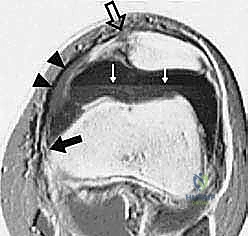

FIG 2F. Transverse gradient-echo image of the knee in a different patient 2 days after lateral patellar dislocation showing partial injury to the femoral origin of the MPFL. The MPFL fibers ( solid white arrow ) are wavy and show longitudinal split, and there is extensive surrounding edema. A complete tear ( open arrow ) is seen in the patellar insertion of the medial patellar retinaculum. A large joint effusion with layering ( black arrows ) is present, consistent with hemarthrosis. Note also the inferior fibers of the VMO ( arrowheads ).